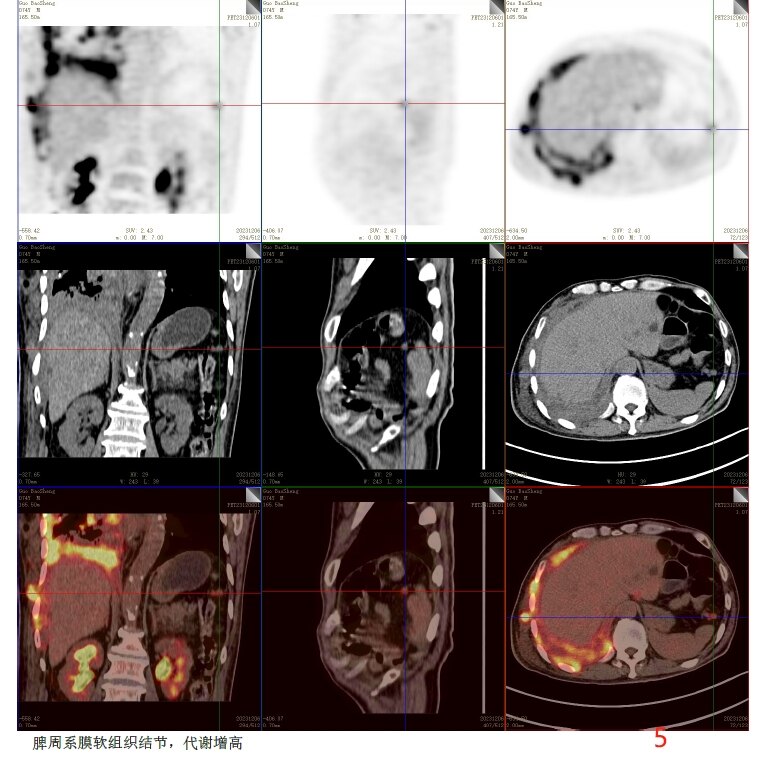

放疗前PET/CT(2023-12-06):

病变层面:

5